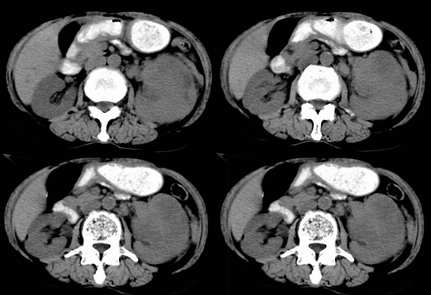

病患,女,69岁,左侧腰部不适,偶感疼痛2个月余,无化验室检查,行彩超发现左侧肾区实质性肿物,后行ct检查,结果同上。

左肾不规则软组织肿块,内见低密度坏死区,与正常肾实质分界不清,左肾明显增大,增强呈不规则条索状强化,肾盂及左输尿管上段扩张。肾周脂肪层受侵、模糊。印象:典型左肾癌。

平扫,表现为肾实质肿块,呈分叶状,肿块密度不均,内有不规则低密度区(陈旧性出血?坏死?)有的似呈囊性,增强明显不均一强化,与肾实质相比呈相对低密度的不均一肿块,肾周脂肪间隙可见,肾前筋膜未见增后,肾血管及腹主动脉旁未见肿大淋巴结影

三期抓的不错,典型的肾癌,且已累及肾盂及左输尿管上段